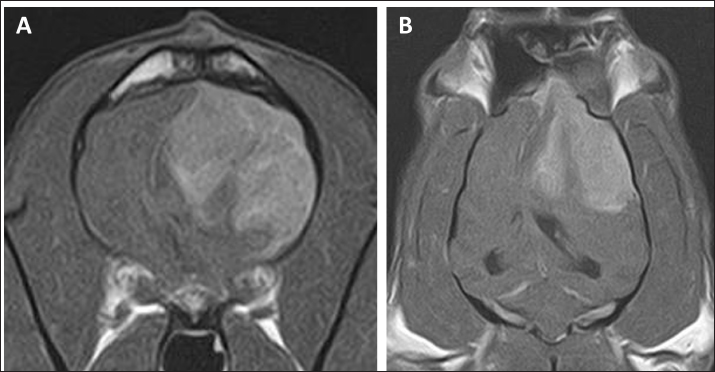

As intracranial disease was suspected in the present case, magnetic resonance imaging (MRI) using a 1.5 Tesla superconducting unit (Vantage Elan, Canon Medical Systems, Otawara, Japan) was performed as further investigation on day 5. MRI revealed a solid mass in the left frontal lobe that the lesion was 32.4 × 29.9 × 27.7 (length × width × height) mm in size showing homogeneous contrast enhancement that shifted the brain midline to the right in contrast enhancement T1-weighted image (T1WI) (Fig. 1A–C). Continuity with the meninges was observed at the tumor margin on contrast-enhanced T1WI. High-signal intensity findings in the brain parenchyma around the tumor indicate edema and/or inflammation on T2-weighted imaging (T2WI) and fluid-attenuated inversion recovery (FLAIR) images. Cerebrospinal fluid was not collected because increased intracranial pressure was suspected based on the MRI findings of transtentorial herniation. MRI findings indicated the possibility of meningioma or HS, and the owner requested surgical volume reduction and medical treatment with anticancer drugs. Radiotherapy was refused because of the cost, and prednisolone (PREDONINE tablets 5 mg; Shionogi & Co, Osaka, Japan) was prescribed at 1 mg/kg once a day until the operation. On day 26, an MRI examination was performed again, revealing that the lesion had grown to 34.7 × 29.9 × 34.9 mm (Fig. 1D–F). The next day, a surgical biopsy due to transfrontal craniotomy was performed to reduce intracranial pressure and confirm the diagnosis. The dog was premedicated with maropitant (1 mg/kg; Cerenia, Zoetis Japan, Tokyo, Japan), fentanyl (3 μg/kg; Fentanyl Injection 0.5 mg, Terumo Corporation, Tokyo, Japan), and lidocaine (2 mg/kg; Lidocaine Intravenous Injection 2%, Terumo corporation), all administered intravenously (IV). General anesthesia was induced with propofol (Propofol Intravenous Injection 1%, Maruishi Pharmaceutical, Osaka, Japan) to facilitate IV until intubation could be performed, following which propofol-based total intravenous anesthesia accompanied by constant rate infusions of fentanyl (10 to 15 μg/kg/hr) and medetomidine (1 to 3 μg/kg/hr; Dorbene, Kyoritsu Seiyaku Corporation, Tokyo, Japan) was administered to maintain anesthesia. Methylprednisolone sodium succinate (10 mg/kg; Solu-Medrol, Pfizer Japan, Tokyo, Japan) and fructose-supplemented glycerol (GLYCEOL for I.V. Infusion, TAIYO Pharma, Tokyo, Japan) were administered IV for 30 minutes to ensure neuroprotection and intracranial pressure reduction, respectively, during the intraoperative period. Although the tumor was visible on craniotomy, it bled easily, and only a small amount of tissue was collected. MRI was performed after surgery, but no significant changes were observed in the size of the tumor (Fig. 2). After the procedures, the patient was allowed to recover from anesthesia and emerged uneventfully 1 hour after extubation. Postoperative management comprising a crystalloid fluid infusion, prednisolone (2 mg/kg once a day), and zonisamide (Epiless tablet, Kyoritsu Seiyaku Corporation, Tokyo, Japan) at 3 mg/kg twice daily was additionally prescribed.

Fig. 1. Postcontrast transverse (A, D, G), dorsal (B, E, H), and sagittal (C, F, I) T1WI of the case. Each image revealed a solid mass in the left frontal lobe.

On day 99, the patient presented with acute onset of somnolence and recumbency. Cerebral infarction was suspected because the entire right cerebral hemisphere and part of the thalamus showed high signal intensity on T2WI and FLAIR images, high signal intensity on diffusion weighted Imaging (DWI) images, and equal signal intensity on the ADC map (Fig. 4). MRI at this time demonstrated that the HS lesion in the left frontal lobe was 28.1 × 24.3 × 22.2 cm in size and had clearly regressed (Fig. 1G–I). The patient was also prescribed rivaroxaban (0.25 mg/kg, twice a day; Xarelto tablets 10 mg; Bayer Yakuhin, Osaka, Japan), and the owners were instructed to perform follow-up at home. The patient's neurological symptoms gradually improved, and a third dose of ACNU was administered at 20 mg/m2 on day 110. However, on day 124, an MRI was performed because a neurological examination revealed a decrease or loss of facial sensation, and trigeminal nerve injury was suspected. Although a contrast agent could not be used because the procedure was performed without anesthesia, clear re-enlargement of the HS lesions was observed (Fig. 5). ACNU was therefore changed to temozolomide (Temozolomide Tablets 20 mg “NK,” Nippon Kayaku, Tokyo, Japan), which was administered at an oral dose of 120-140 mg/m2 once daily for 5 days over a 28-day cycle on day 131, 153, and 173. During this time, there were no major changes in the patient's clinical symptoms, and the patient was able to walk with some unsteadiness. However, the patient died suddenly on day 195. A pathological autopsy was not performed at the owner's request.

In the present case, the reduction of the tumor lesion was confirmed by MRI following the second administration of ACNU. CCNU, an alkylating drug belonging to the nitrosourea family, is often used as a first-line drug therapy for the treatment of HS in dogs, with a response rate of 29% and a response duration of 96 days for gross lesions (Rassnick et al., 2010). In six dogs with HS at various sites treated with ACNU as a single agent, the response rate was 50%, with a median response duration of 48 days (Takahashi et al., 2023). In the present case, the administration of ACNU resulted in tumor reduction. The duration of the effect was short, lasting 84 days; however, the clinical symptoms improved during that time. To the best of our knowledge, this is the first report showing the macroscopic reduction effect of ACNU on intracranial HS in dogs.